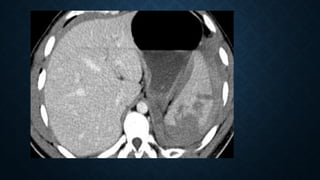

• Axial CECT scan shows

nonenhancing spleen

• Axial CECTscan shows nonenhancing spleen